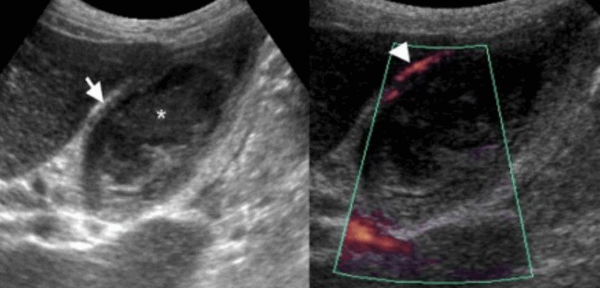

(Слева) На поперечной трансабдоминальной сонограмме в ямке желчного пузыря визуализируется эхогенная структура изогнутой формы с акустической тенью — изменения, характерные для «фарфорового» желчного пузыря.

(Справа) На сонограмме визуализируется стенка желчного пузыря с диффузно повышенной эхогенностью и объемное образование в области его дна. Задняя стенка желчного пузыря различима, в отличие от эмфизематозного холецистита или множественных камней, заполняющих желчный пузырь. При патоморфологическом исследовании были обнаружены интрамуральные кальцинаты, признаки хронического холецистита и аденокарциномы желчного пузыря.

(Левый) Пример полного кальциноза: у пациентки 67 лет, жалующейся на периодические боли в области желчного пузыря, при сканировании в черно-белом режиме в ямке желчного пузыря определяется тонкая гиперэхогенная полулунная линия, отбрасывающая плотную акустическую тень.

(Правый) У этой же пациентки в той же области в правом верхнем квадранте ожидаемо определяется диффузная криволинейная линия кальциноза, повторяющая контуры желчного пузыря.